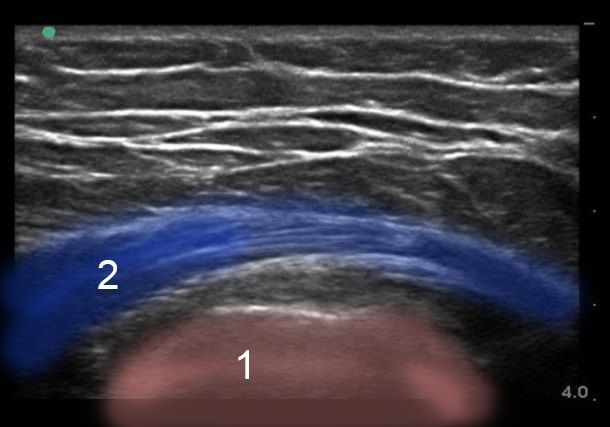

Imagen 1 de la vista transversal de la fascia lata en el lateral de la cadera

1. Trocánter mayor

2. Fascia lata